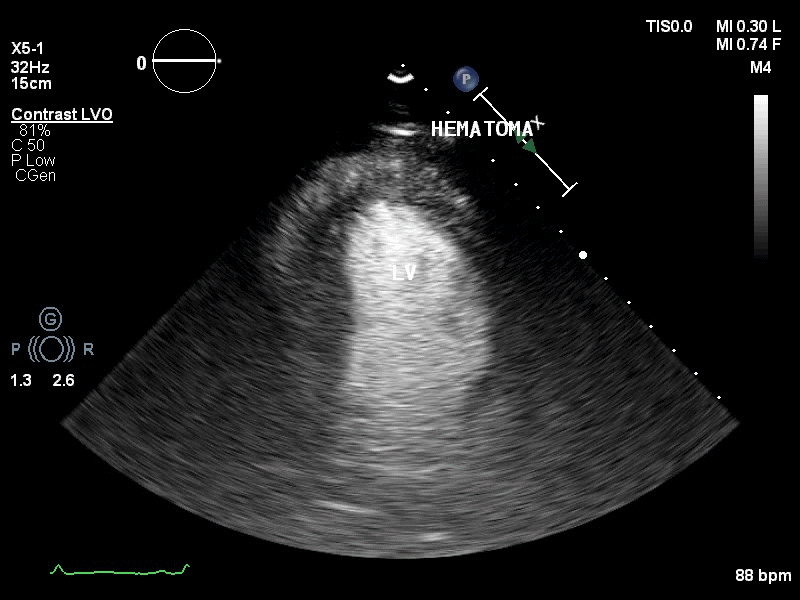

视频1:左室心尖可见团块状低回声,疑似血肿。

为进一步明确诊断,行床旁心脏超声造影,可见Contrast-LVO模式下,可见心包腔内可见由左室心尖缓慢飘出的点状造影剂声像。

视频5-6 :心脏超声造影提示:右室流出道与左室心尖间外壁血肿形成。中大量心包积液。

图5: 2017年8月30日复查经胸超声心动图提示:左室靠近心尖处血肿形成。少量心包积液。左室靠近心尖处外壁可见一低回声包块,大小约40mmx21mm,边界尚清。